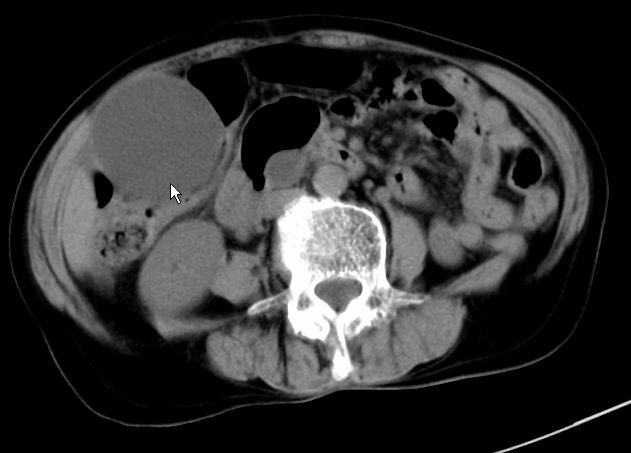

以下是引用zjzjr在2008-12-16 12:49:00的发言:[br]肝内外胆管全程扩张,胆囊明显增大,未见占位征像.建议mrcp.

以下是引用jiangjing在2008-12-16 13:19:00的发言:[br]肝内外胆管全程扩张,胆囊明显增大,扩张胆总管下段径较中上段小,未见胰管扩张,提示胆总管远端梗阻伴感染.建议增强及mrcp 检查

以下是引用朱亮在2008-12-16 12:54:00的发言:[br]胆总管远端应薄层扫描 胆总管逐渐变细 考虑胆系慢性炎症